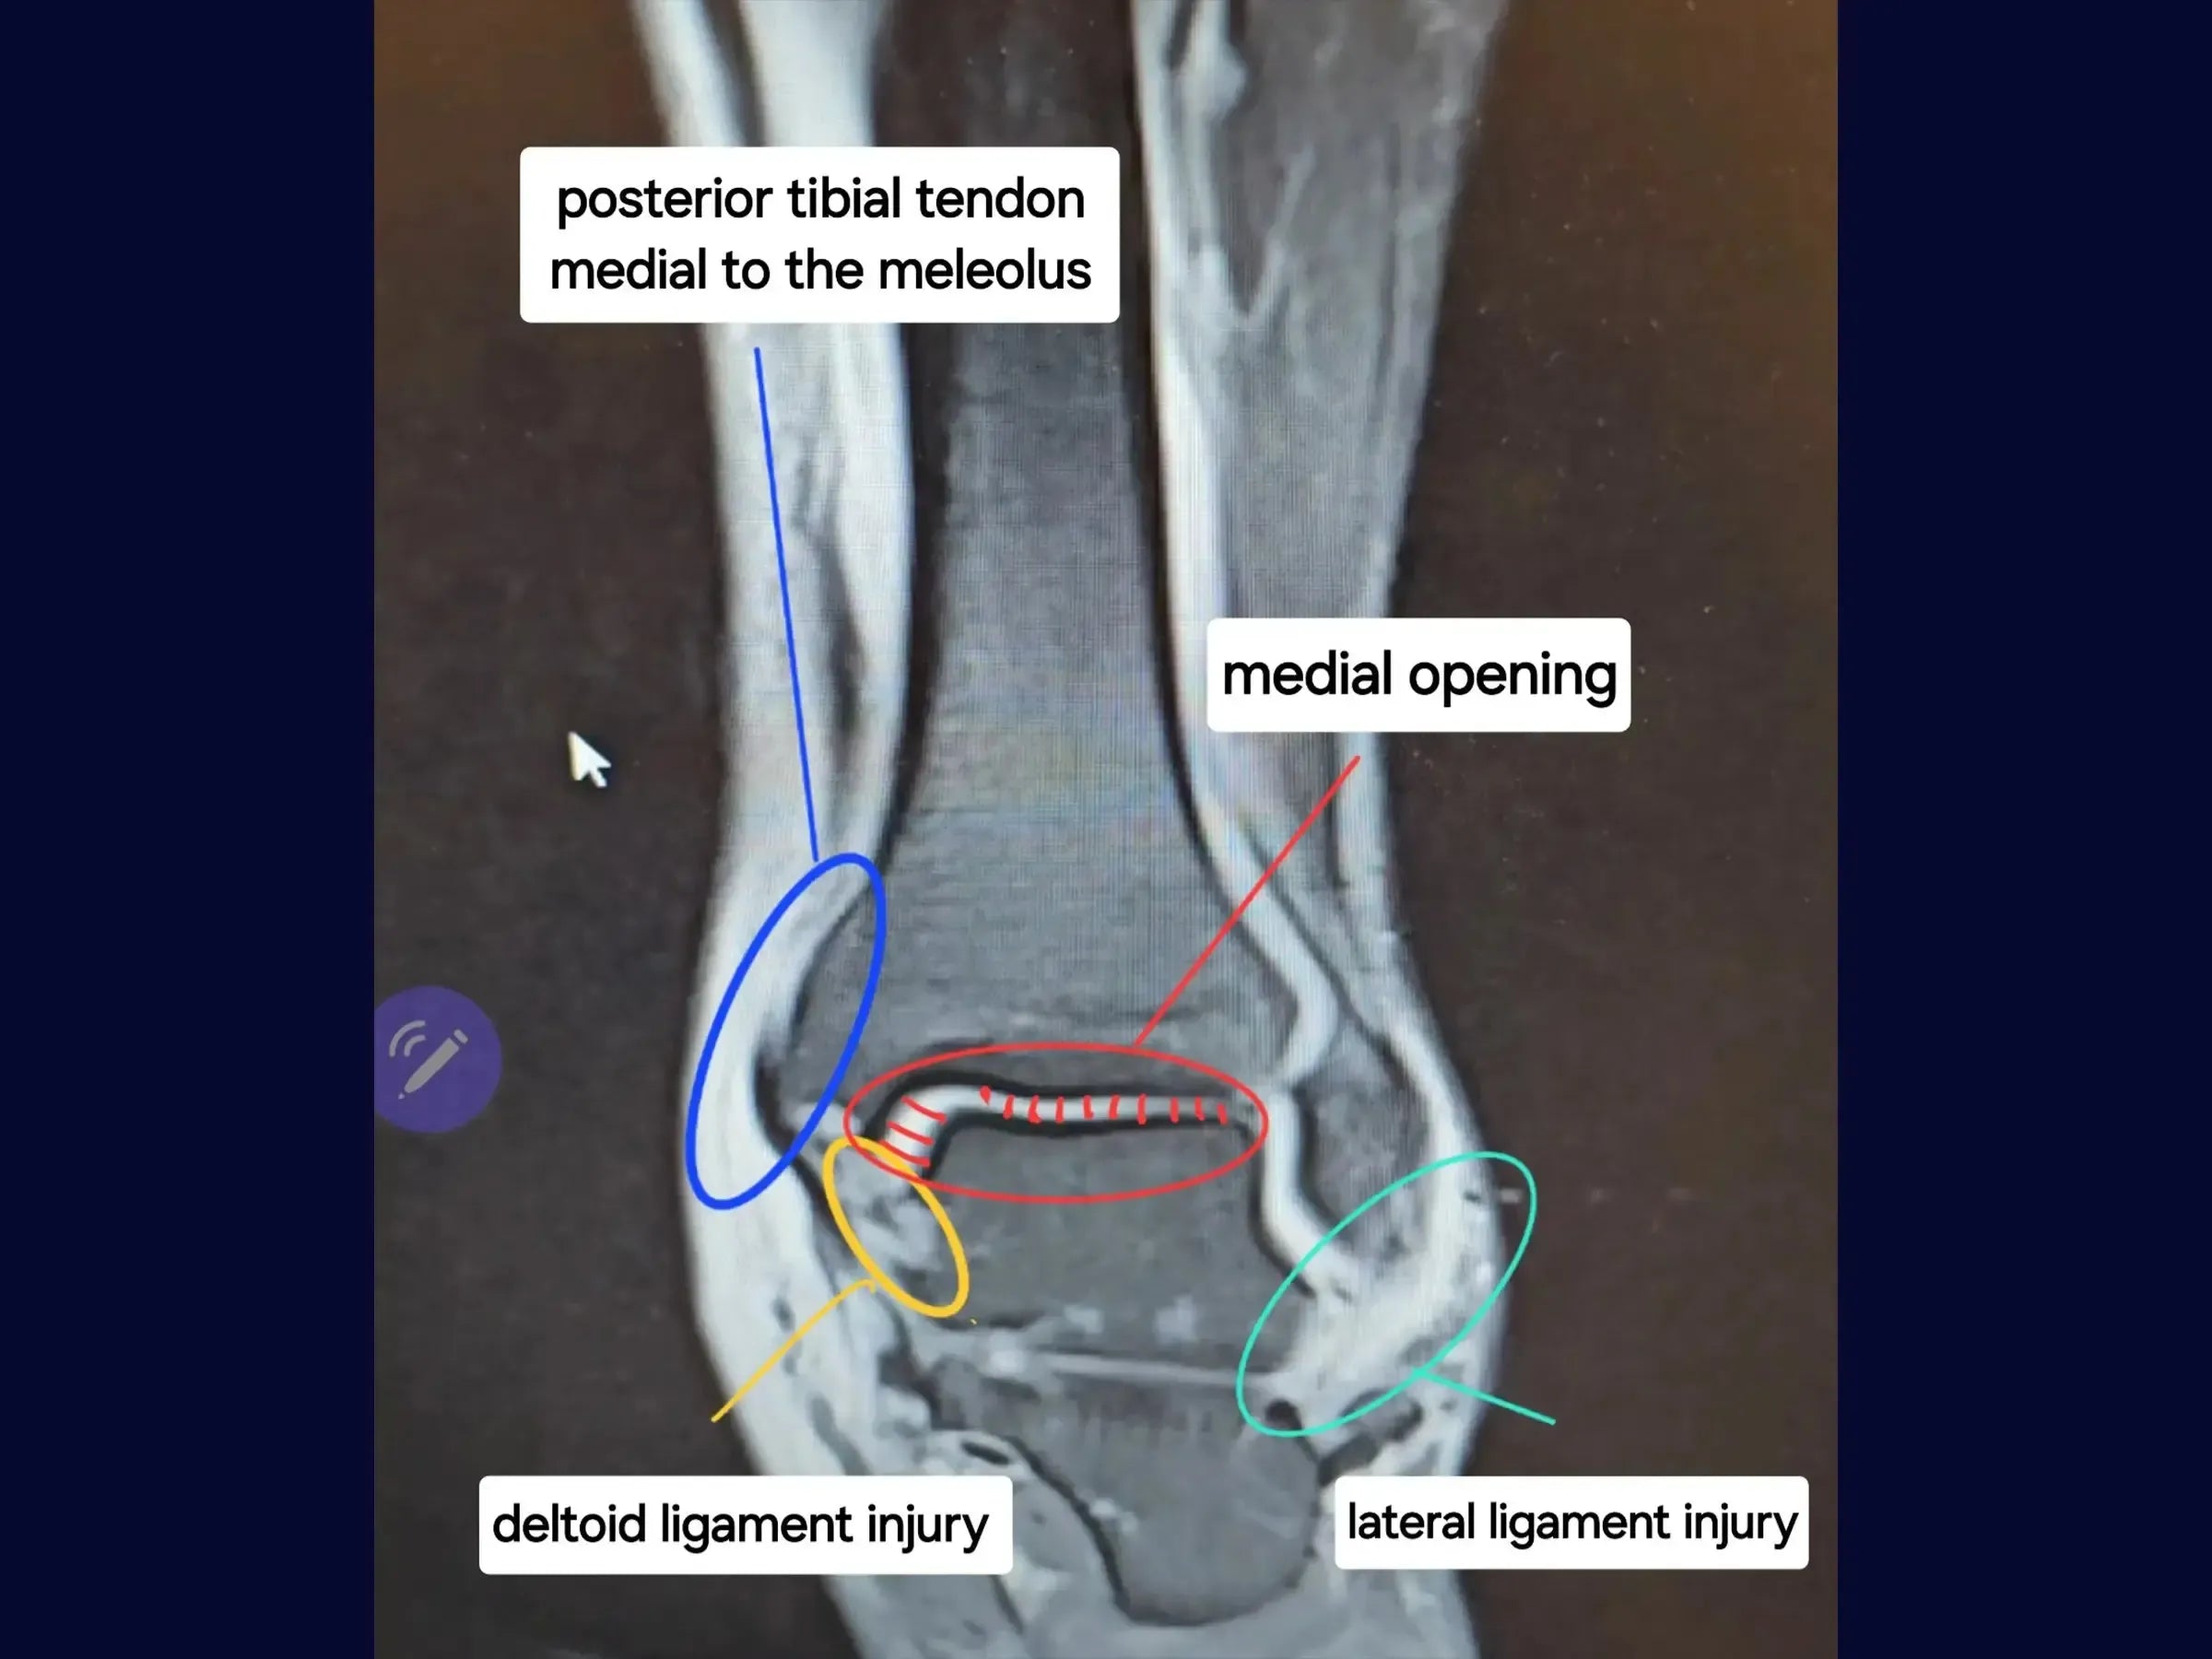

- Restauración del tendón tibial posterior: abordaje para la reinserción del tendón tibial posterior dislocado en su surco original, incluida la reparación del retináculo desgarrado para restaurar la biomecánica funcional.

- Reconstrucción detallada del ligamento (deltoides y sindesmosis): técnicas de reinserción de las porciones anterior y posterior del ligamento deltoides con anclajes y estabilización de la sindesmosis con un dispositivo de fijación.